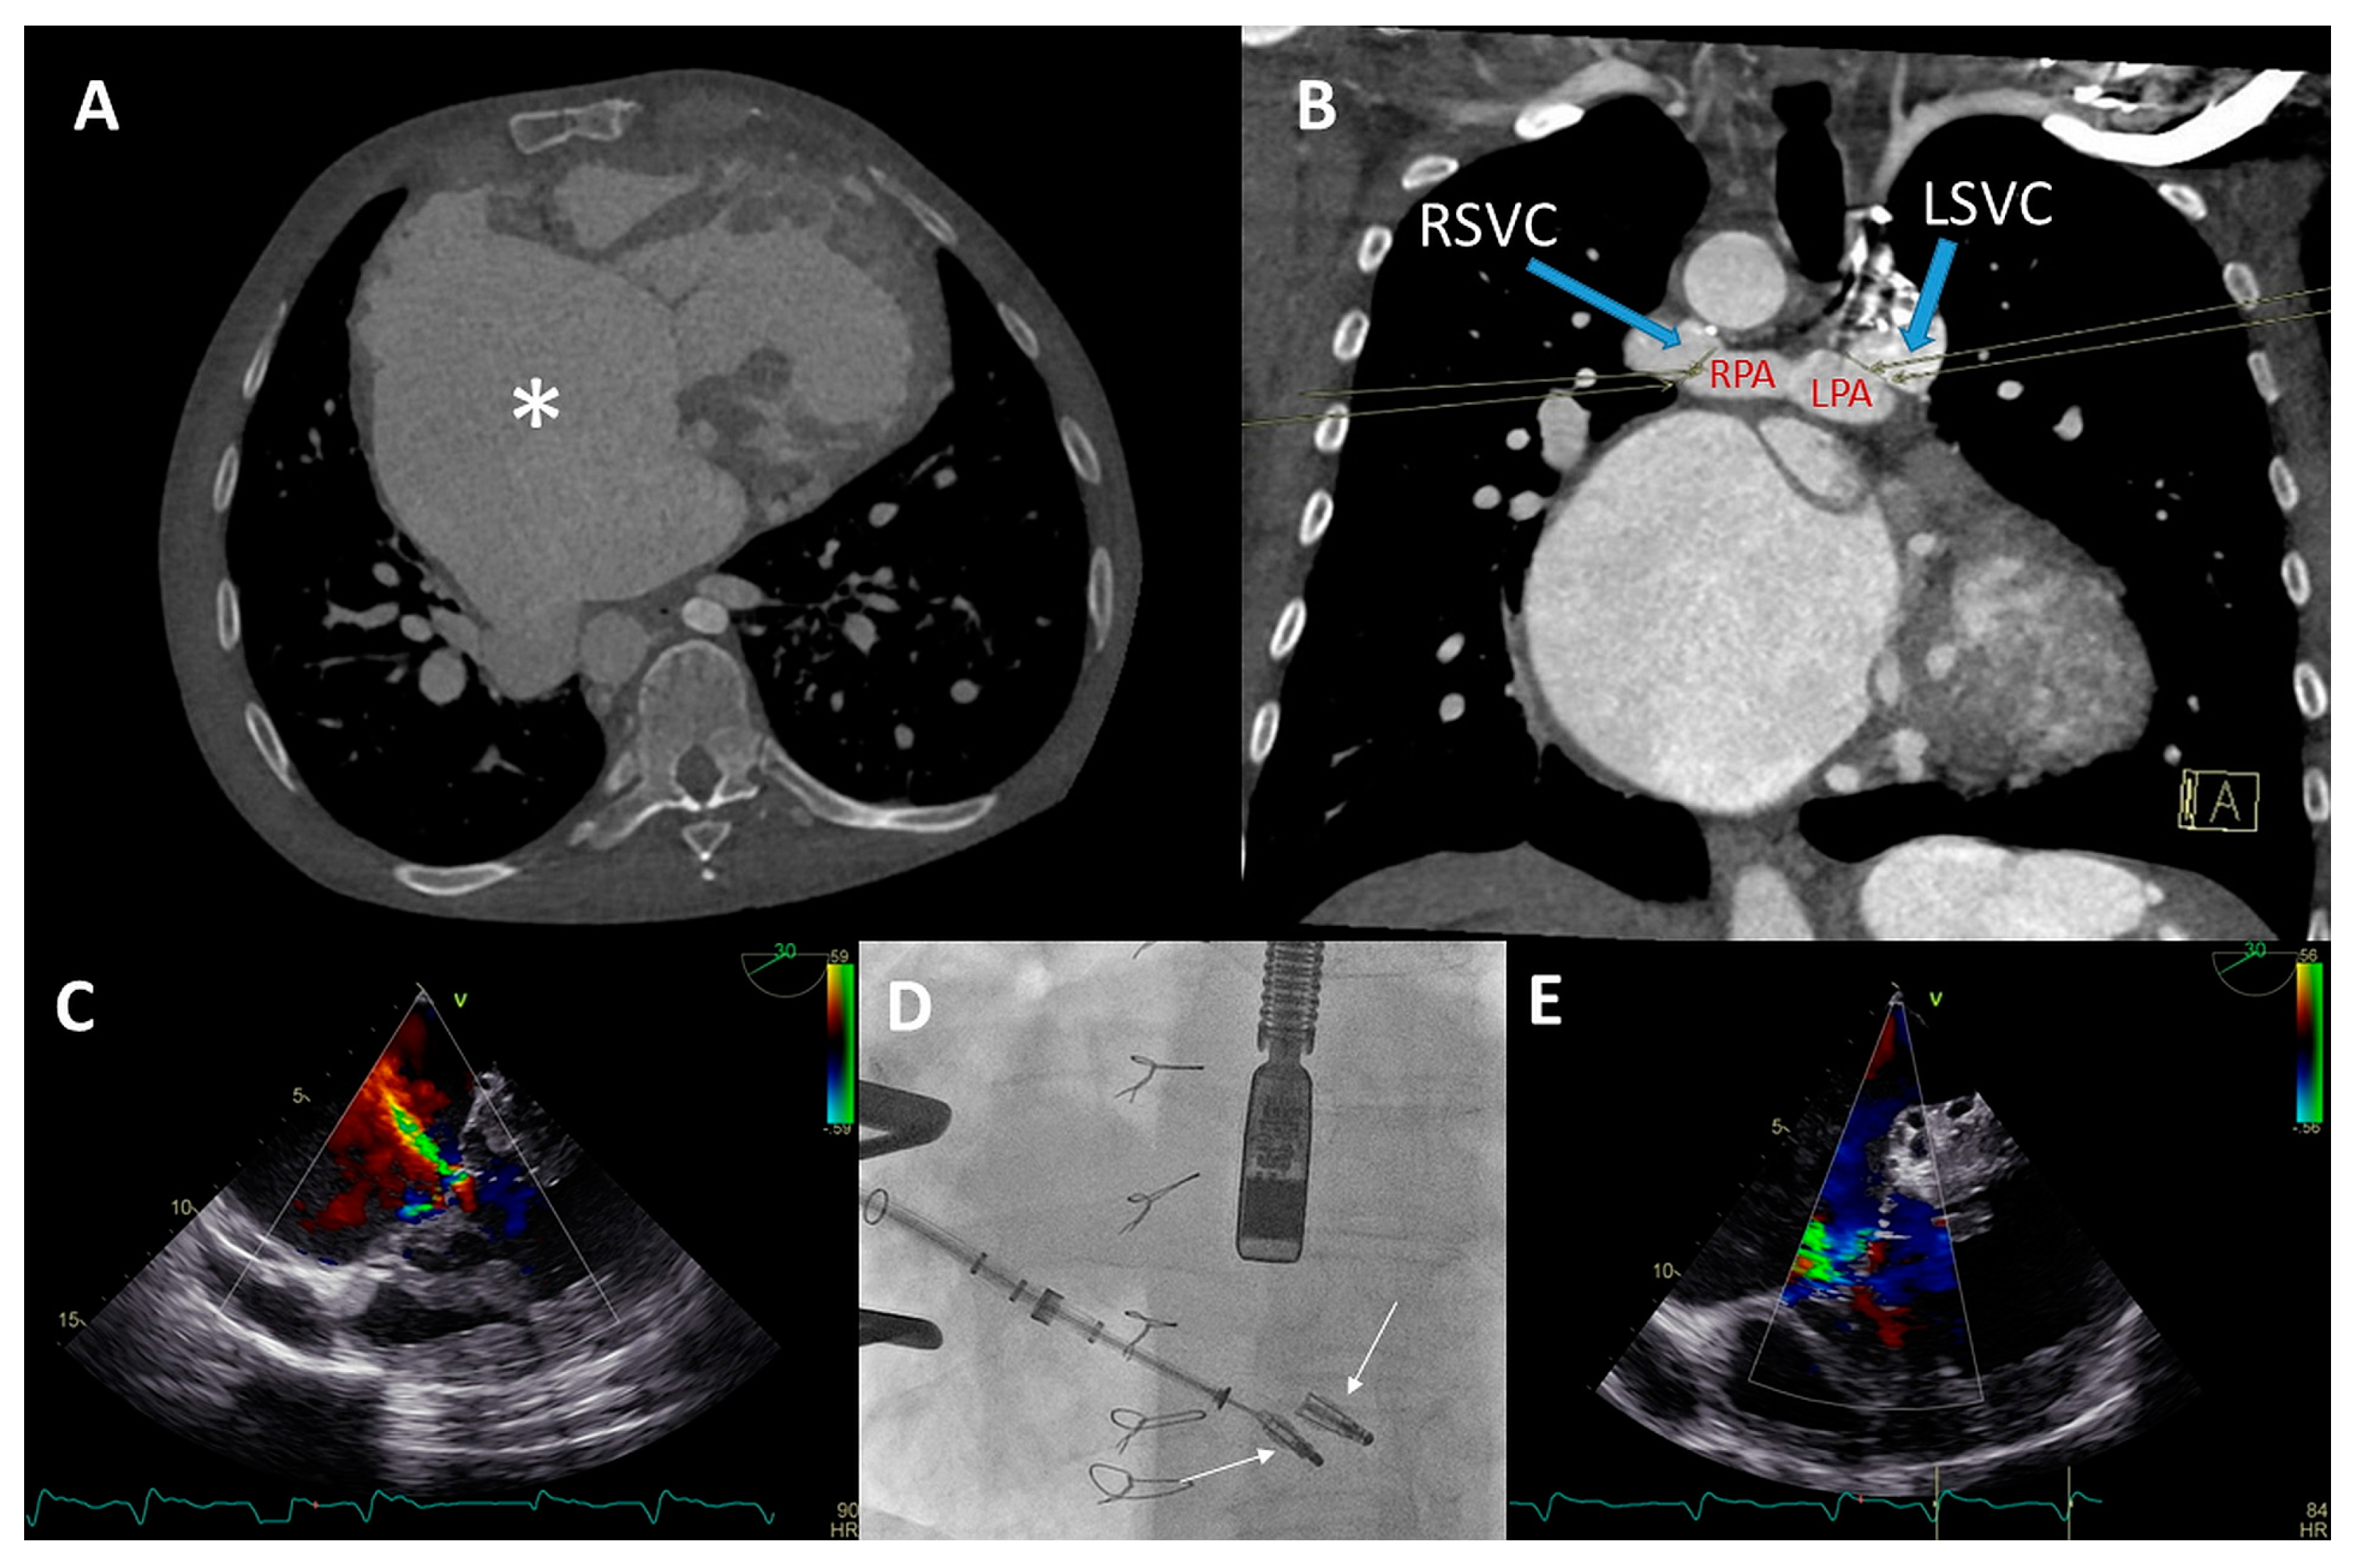

Figure 7.

(A) Color Doppler modified parasternal right ventricular (RV) inflow view shows severe tricuspid regurgitation (TR) with a wide vena contracta (arrow) and leakage jet reaching the inferior vena cave (IVC). (B) Apical four-chamber view shows tricuspid valve (TV) annulus dilatation (dash line, 46 mm) and impingement by the RV pacemaker lead (arrow). (C) Left inferior oblique fluoroscopic view of the Cardioband (arrow) annulus reduction procedure (asterisk). (D) Anteroposterior fluoroscopic view shows the two XTW clips (arrows) implanted. (E,F) Modified apical four chamber color Doppler views showing mild (-moderate) residual TR and inflow through the TV (mean gradient of 3 mmHg).

Both procedures were performed in sequential order under general anesthesia, by means of right femoral access and fluoroscopy and transesophageal echocardiographic guidance (Figure 7C,D). A total of 15 anchors were used for the Cardioband annular reduction (Edwards Lifesciences, USA) reducing the annulus dimensions to 28 × 27 mm. Yet, moderate-severe TR persisted and the second procedure was planned for the patient. She underwent the placement of two TriClips (Abbott, IL, USA), resulting in reduction of TR to mild-moderate and a slightly elevated inflow gradient of 3 mmHg over de TV (Figure 7E,F). No periprocedural complications were documented. At 16 months follow-up, the patient remains in NYHA functional class II and is euvolemic. No heart-failure-related admissions occurred since the TV interventions.